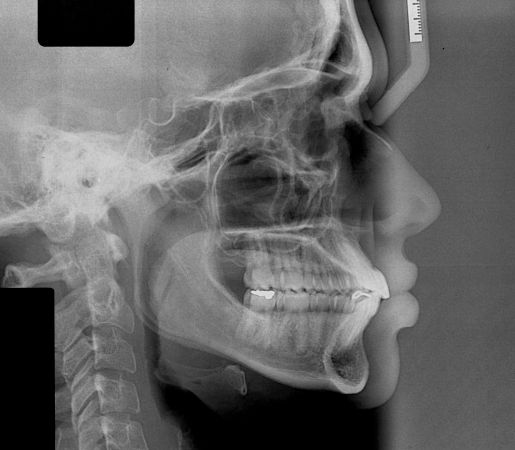

Tratamento da maloclusão de Classe III com elásticos intermaxilares e controle mecânico do arco inferior